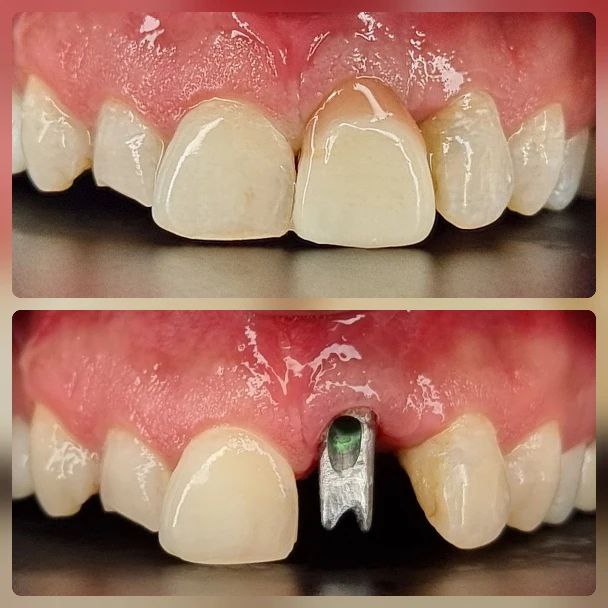

کاشت ایمپلنت دندان

اطمینان حاصل کردن از اینکه دندانهایتان به نحوی زیبا و طبیعی جایگزین شدهاند، از اهمیت بسیاری برخوردار است. ایمپلنت دندان به عنوان یک روش درمانی دائمی در دندانپزشکی شناخته میشود که حاصل آن، یک دندان زیبا و طبیعی در دهان شما خواهد بود.

هرچند که این روش درمانی هزینهی بیشتری نسبت به روشهای دیگر دارد، اما ارزش زیبایی که ایجاد میکند، قابل انکار نیست. ایمپلنتها به قدری شبیه به دندانهای طبیعی هستند که به سختی میتوان آنها را از دیگر دندانها تشخیص داد.